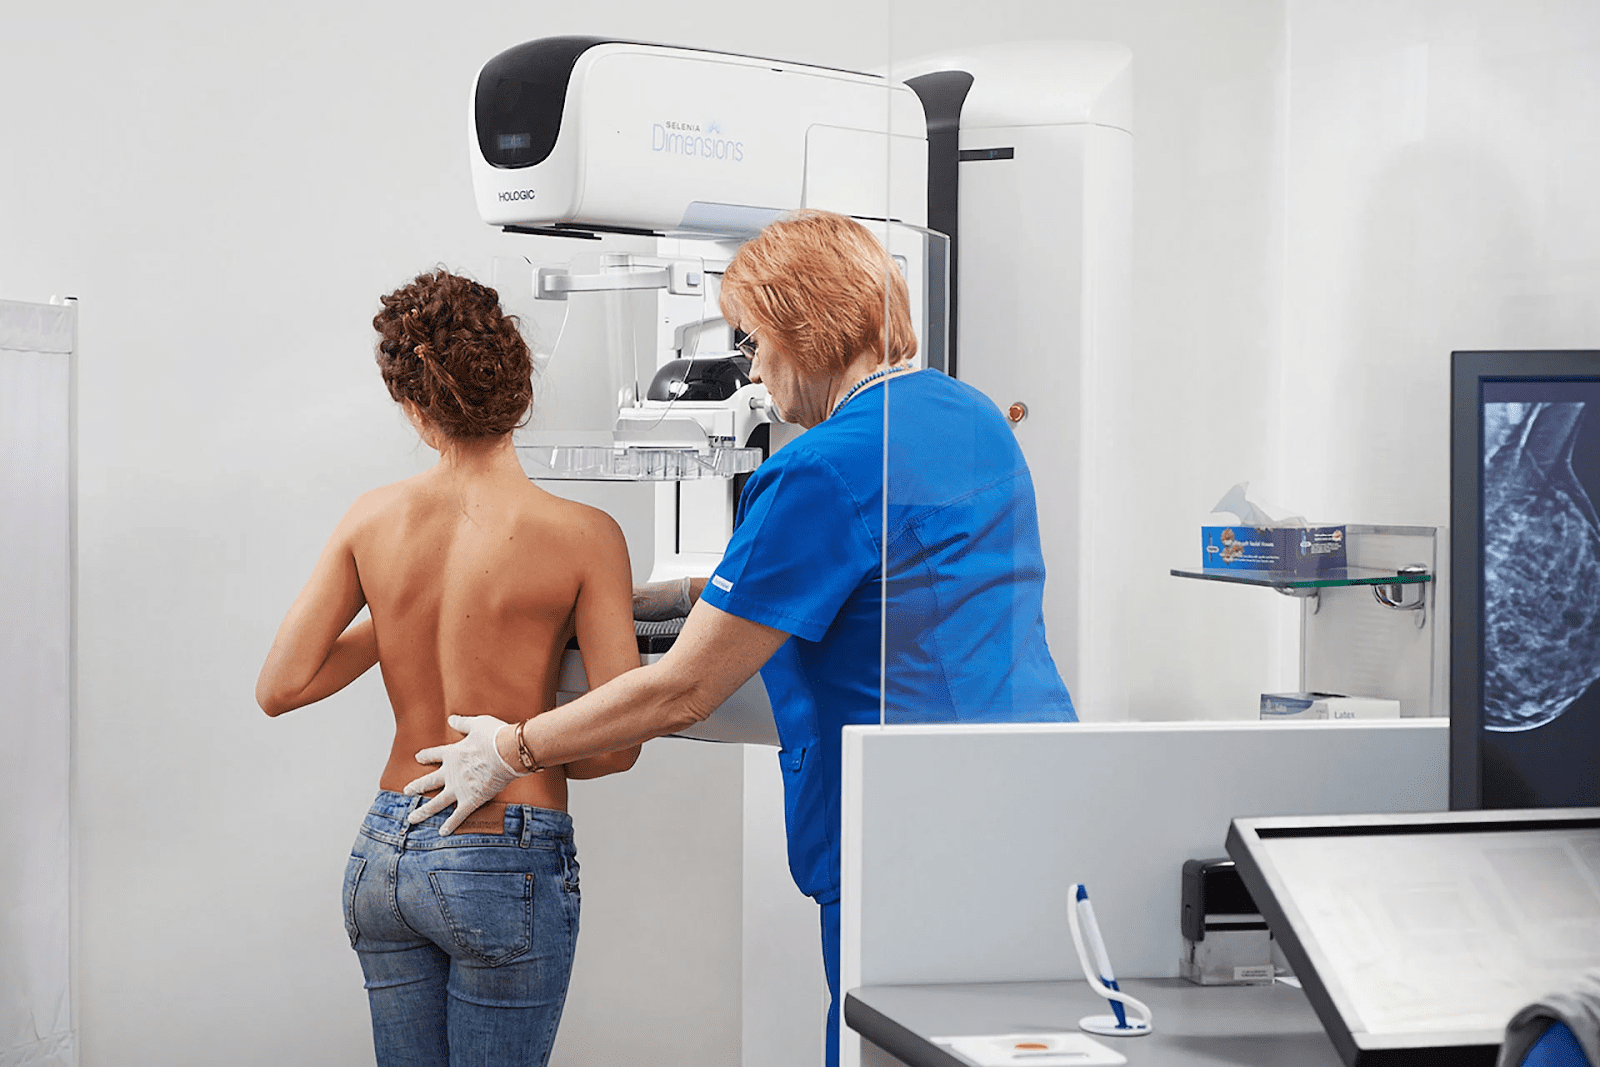

Это часть программы скрининга рака молочной железы Альберты, которая предлагает маммографию и информацию о здоровье груди женщинам в Эдмонтоне и в 120 общинах Альберты. Это очень интересный проект, ведь у службы есть 2 мобильные маммографические клиники на колесах, которые укомплектованы необходимым оборудованием для удобной диагностики.

Женщины Альберты от 45 до 74 лет имеют право на бесплатную маммографию каждые два года. Если вам от 45 до 74 лет, вас автоматически включают в программу скрининга. Если вам исполнилось 50 лет и вы не проходили маммографию в Альберте, вы получите письмо, которое приглашает вас пройти обследование.

Процесс маммографии в центре проходит очень комфортно. Когда вы придете на приём, вас попросят переодеться в халат. Чтобы получить четкое изображение, технолог разместит вашу грудь на компрессионную пластину, а аппарат постепенно сжимает грудь между двумя пластинами. Это может привести к небольшой дискомфорт, но это важно для четкого изображения. Если у вас очень чувствительная грудь, рекомендуется приходить по меньшей мере за неделю до менструации.